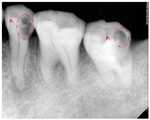

상기 획득된 X-Ray 치아 이미지에 대해 전처리 모듈이 전처리를 수행하여 도 3a와 같이 원 이미지(I0)를 생성한다.(S120)The preprocessing module performs preprocessing on the obtained X-ray tooth image to generate an original image I0 as shown in FIG. 3A.

도 3b는 이진 처리된 이진 이미지(Ib)를 도시한 것이고, 도 3c 는 3배를 곱해 생성된 3배 이미지(3I0)를 도시한 것이다.FIG. 3B shows a binary processed binary image Ib , and FIG. 3C shows a triple image 3I0 generated by multiplying three times.

도 3a의 원 이미지(I0)와 도 3f의 최종 치아우식 이미지(Is0-I(rsb-30))를 육안으로 비교해도 알 수 있듯이, 원 이미지 만으로는 치아우식증 정보에 대한 육안 판별이 불가능 하지만 최종 치아우식 이미지(Is0-I(rsb-30))는 원 이미지에 비해 이미지 선명도가 대폭 증가되어 육안으로 치아우식증 정보 판단이 가능하며, 이를 통해 치아우식증 진단이 가능하다.As can be seen by visually comparing the original image (I0 ) of FIG. 3A and the final dental caries image (Is0 -I(rsb-30) ) of FIG. 3F, the visual identification of dental caries information is not possible using the original image alone. The final dental caries image (Is0 -I(rsb-30) ) is significantly increased in image sharpness compared to the original image, so that the dental caries information can be determined with the naked eye.

상기 모든 이미지 변환 과정을 통해 획득된 최종 치아우식 이미지(Is0-I(rsb-30))의 진단의 장점은 도 3a의 P1, P2의 부분을 치과생리해부학적 구조에 의해 치아우식증의 증상 유무를 판단하기에 다소 주관적인 것을 상기 모든 이미지 변환 과정을 거쳐 도 3f의 P1', P2'로 이미지 개선 변환되어 구강악안면방사선과에서 구내방사선영상을 육안으로 치아우식의 소견을 객관적으로 판단하는 것이 가능하다.The advantage of the diagnosis of the final dental caries image (Is0 -I(rsb-30) ) obtained through all the above image conversion processes is that the parts of P1 and P2 of FIG. It is somewhat subjective to judge the presence of symptoms through the above image conversion process, the image is improved and converted into P1 ', P2 ' of Fig. 3f to objectively judge the findings of dental caries by visualizing intraoral radiographs with the oral and maxillofacial radiology department. It is possible.

도 3a는 원 이미지(I0), 도 3b는 상기 원 이미지(I0)의 이진이미지(Ib), 도 3c는 상기 원 이미지(I0)의 3배 이미지(3I0), 도 3d는 이진 이미지(Ib)로부터 3배이미지(3I0)를 디지털 공제 처리(Ib-3IO)를 수행하여 디지털 공제된 이미지(Isb-30), 도 3e는 디지털 공제된 이미지(Isb-30)를 이미지 반전하여 생성된 반전이미지(Irsb-30), 도 3f는 상기 반전이미지(Irsb-30)를 상기 원 이미지(I0)로부터 디지털 공제 처리(I0-Irsb-30)하여 생성된 최종 치아우식 이미지(Is0-I(rsb-30))를 도시한 것이다.Figure 3a is the original image (I0), Fig. 3b shows the original binary image (Ib), Figure 3c triple image (3I0) of the original image (I0), Fig. 3d of the image (I0) is binary image (Ib) 3 times the digital image subtraction process(3I 0) (I b -3I O) the image carried by the digital subtraction (Isb-30), Figure 3e is a digital subtraction image (Isb- from30 is an inverted image (Irsb-30 ) generated by inverting the image, and FIG. 3F illustrates a digital subtraction process (I0 -Irsb-30 ) of the inverted image (Irsb-30 ) from the original image (I0 ). the resulting final dental caries image(s0 I -I(30-rsb)) to illustrate.